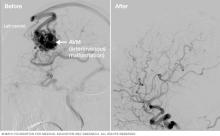

Brain scans showing Gamma Knife surgery results.

Gamma Knife surgery results

Gamma Knife surgery uses multiple tiny beams of radiation to shrink tumors. The left brain scan shows a pretreatment image of a noncancerous tumor — an image enhanced by the use of a special medium, called a contrast agent. At six months after treatment (middle image), the tumor appears slightly larger but doesn't take up as much of the contrast medium — it isn't as bright in the center. This indicates a positive treatment effect. At seven years (right scan), the tumor appears much smaller.